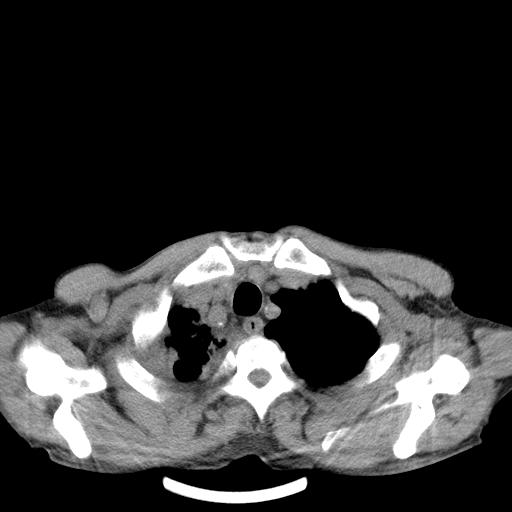

男性 75  咳嗽 一周前发热最高达39

右肺继发型tb并右侧tb性胸腔炎,右侧胸腔大量积液并右下肺膨胀不全,慢支肺气肿、多发肺大泡。建议抽胸水实验室检查并复查排除恶性在占位。

右上肺继发型肺结核,右胸腔中等量积液。

左上肺大泡。

结核的基础上有纵隔淋巴结肿大,右侧有胸水,但右侧纵隔反而窄,说明有肺有不张。

再就是右下肺有块影,和不张混合,还是不能除外肺癌。

补充材料,患者2月份ct片大致正常,双侧胸腔积液,2月份抽胸水未发现ca细胞,现患者发热,痰多,各气管通畅,

1)右肺继发型肺结核。2)左肺胸膜下多发性肺大泡。3)右侧胸腔积液。